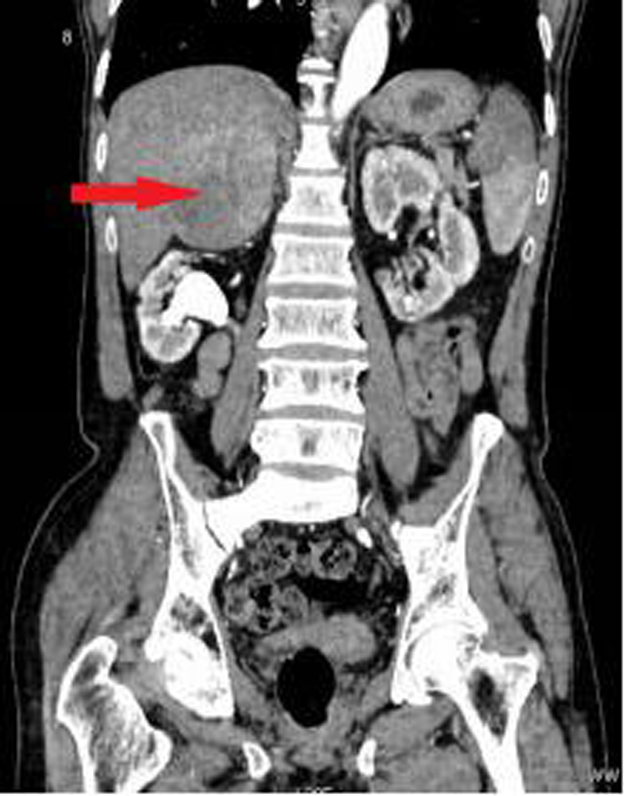

(右侧肾上腺肿瘤CT图示,红色箭头)

(右侧肾上腺肿瘤CT图示,红色箭头)功能性肾上腺肿瘤之嗜铬细胞瘤